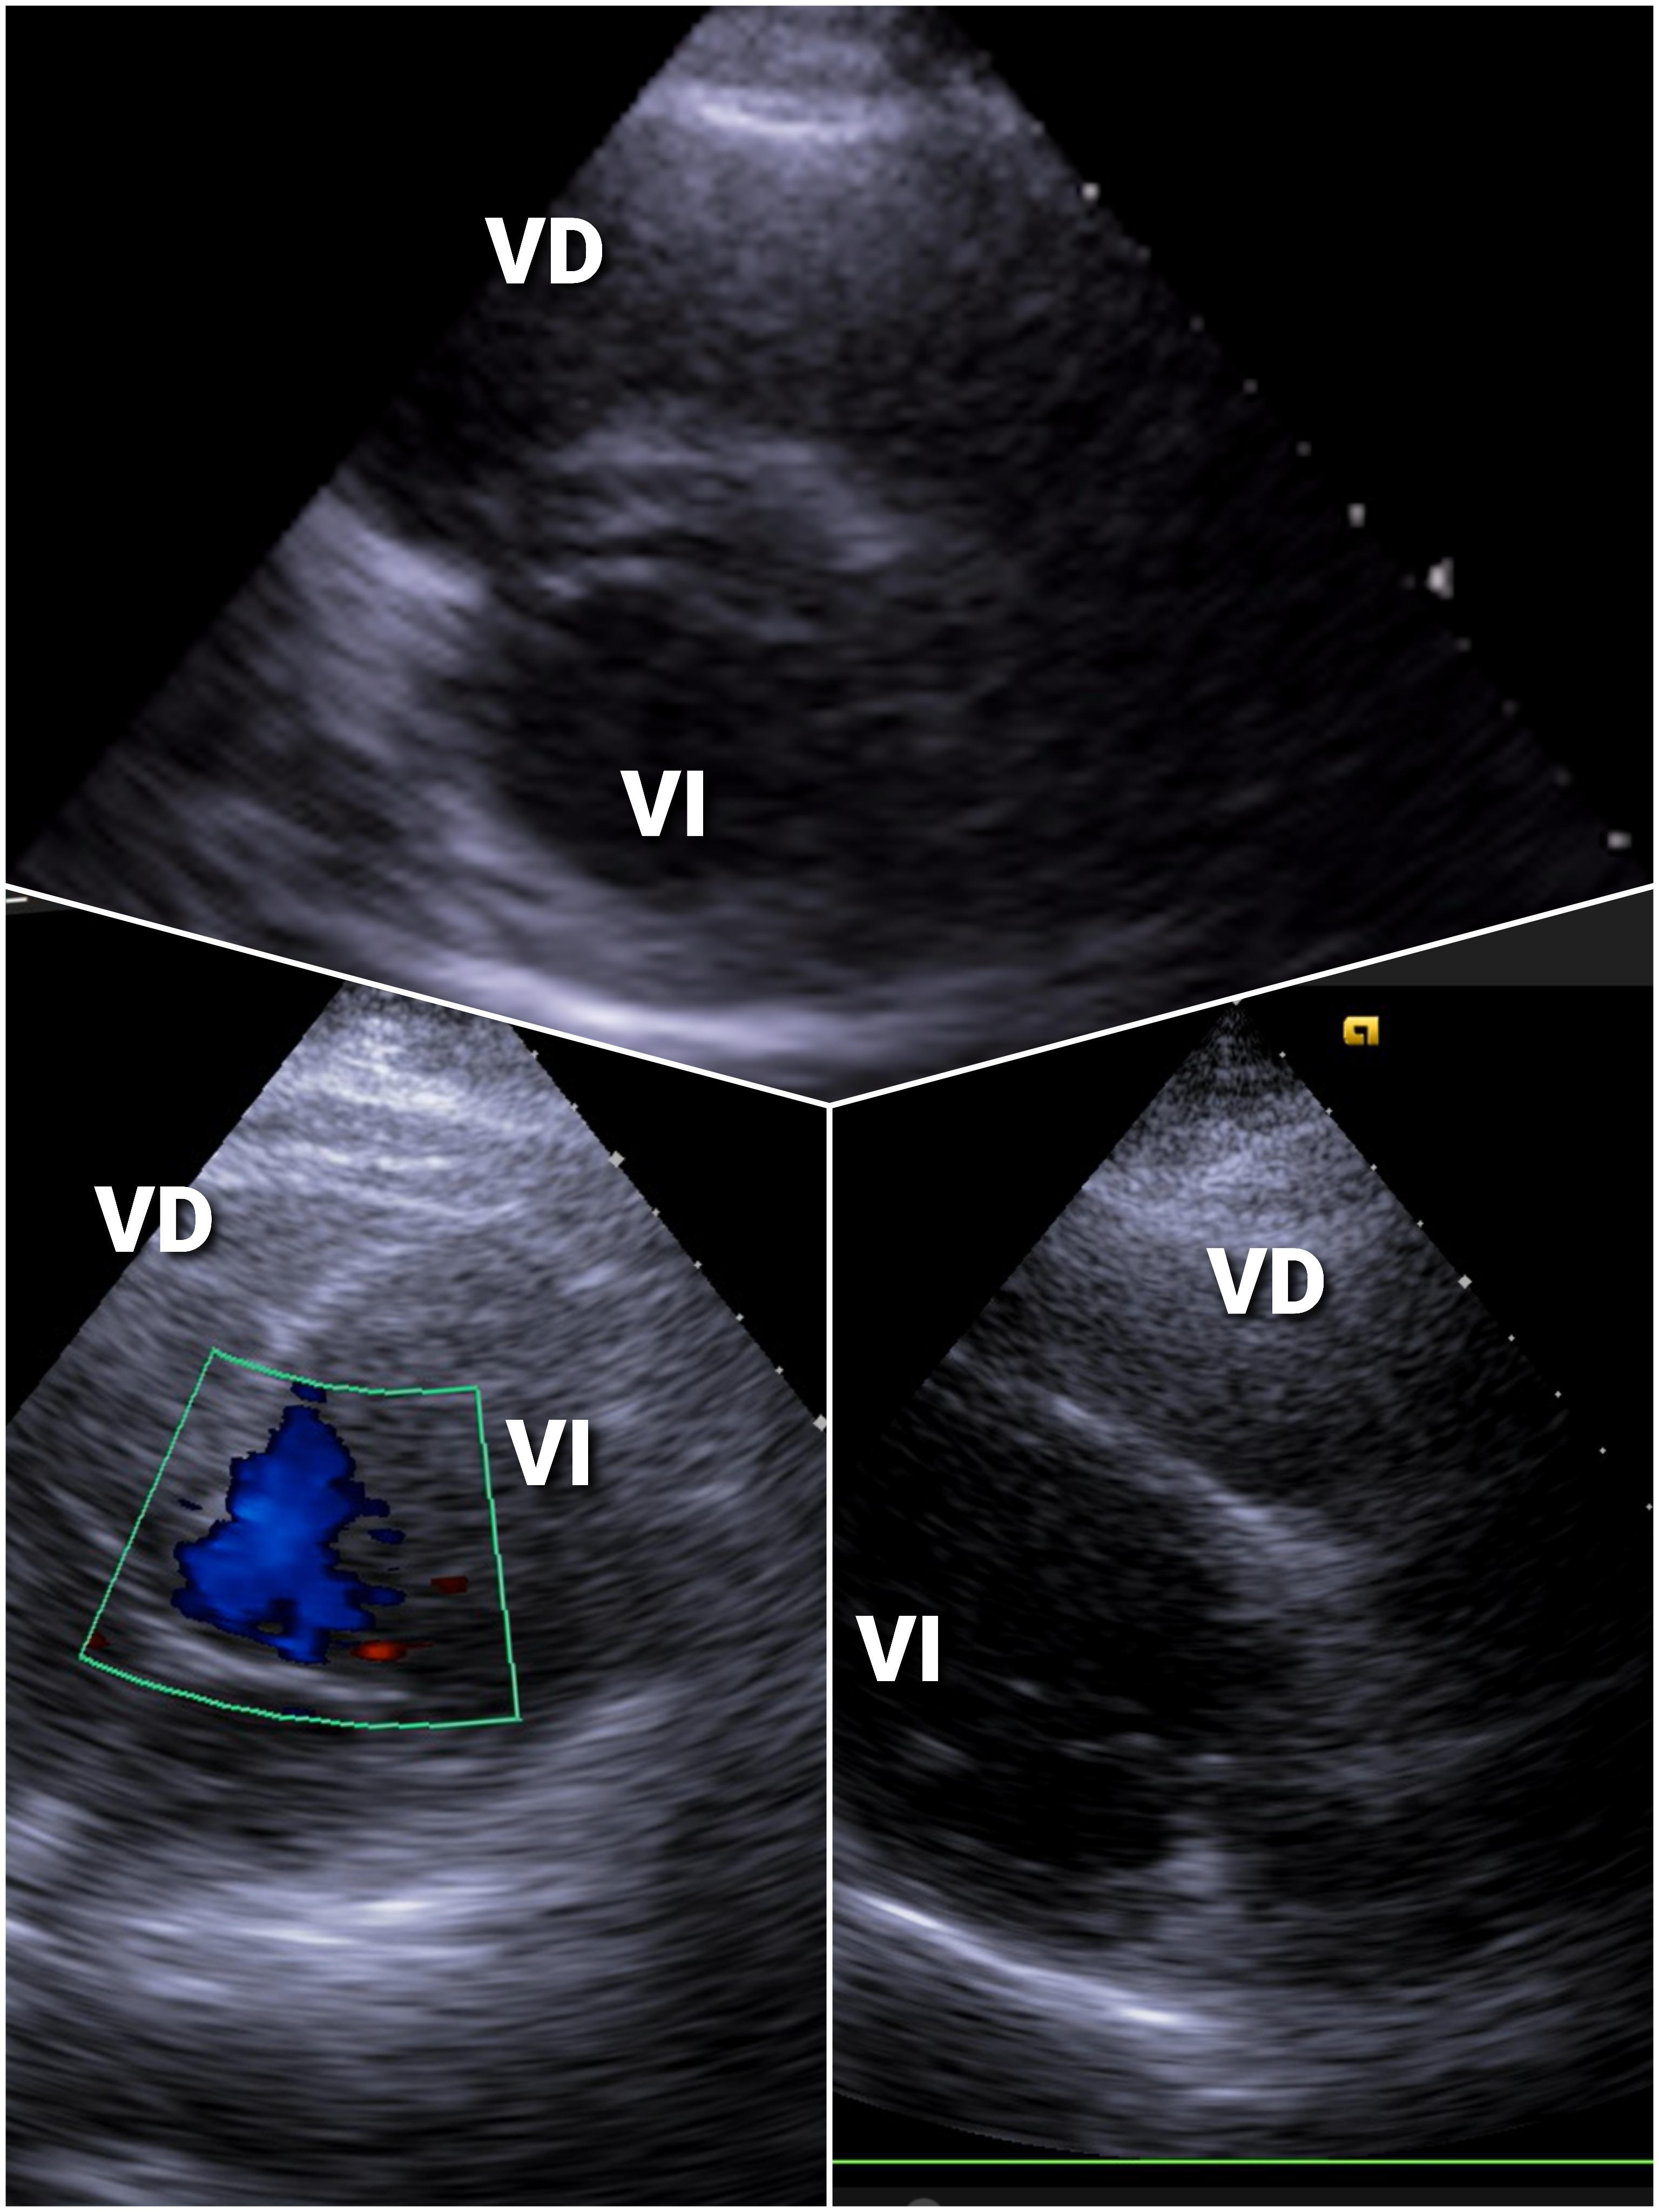

EcoCardioscopia: contractilidad preservada sinvalvulopa tías ni aumento de cavidades derechas.

Trombosis Venosa Profunda (TVP) Poplítea con sospecha de Embolismo Pulmonar (EP)

Remitido a urgencias hospitalarias con orientación diagnóstica de TVP con sospecha de TEP.